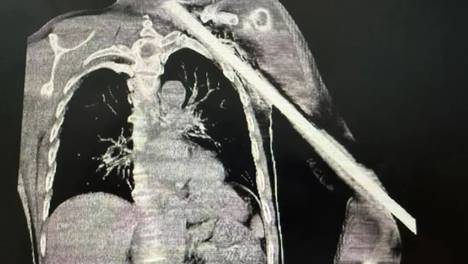

一根粗壮的钢筋……7月14日被钢筋穿入身体的男子因裸露在外的😢钢筋影响后续检查和救治在医生和消防员的协同配合下消防员用液压🤔剪小心翼翼地剪切钢筋外部裸露的一截钢筋希望大家都能远离此类伤😅害倘若不幸被利器贯穿受伤谨记…